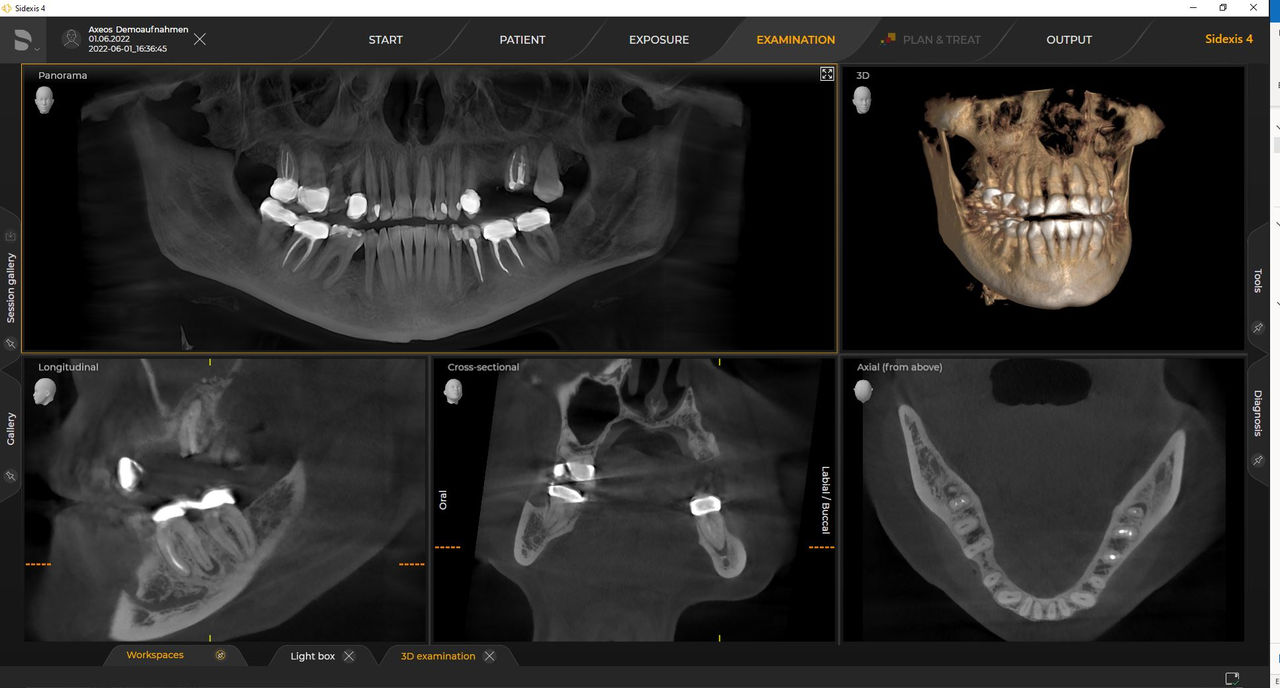

Las unidades 3D de Dentsply Sirona funcionan exclusivamente con Sidexis 4. Sin embargo, la migración de datos de Sidexis XG a Sidexis 4 es muy fácil. Sidexis 4 permite una experiencia digital completa con las últimas herramientas.